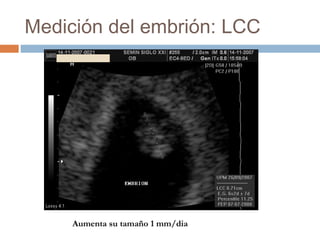

Medición del embrión: LCC

Aumenta su tamaño 1 mm/dia

ECOGRAFIA DEL EMBARAZO INTRAUTERINONORMAL LONGITUD CRANEOCAUDAL. Es posible visualizarlo vía transvaginal a partir de la semana 5. POR VIA TRANSABDOMINAL A PARTIR DE LA SEMANA 6

ECOGRAFIA DEL EMBARAZO INTRAUTERINONORMAL LONGITUDCRANEOCAUDAL Durante la semana 6, con el plegamiento ventral de los extremos craneal y caudal cambia de un disco aplanado a una estructura en forma de “C”.

Medición del embrión:LCC Aumenta su tamaño 1 mm/dia